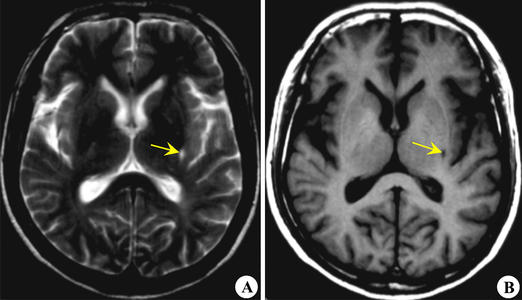

腔隙性脑梗死和脑梗死的主要区别就是梗死的面积小、症状轻微(头晕),很多患者可能都没有症状,只是在体检的时候才发现自己有腔隙性脑梗死。

腔隙性脑梗死的病灶多在3~4mm,小的梗死灶可能只有0.2mm,但是大的梗死灶能达到20mm。虽然说腔隙性脑梗死的梗死面积小,但是这也不是就说它的症状一定就轻,因为它的症状还和脑梗死发生的部位有关。